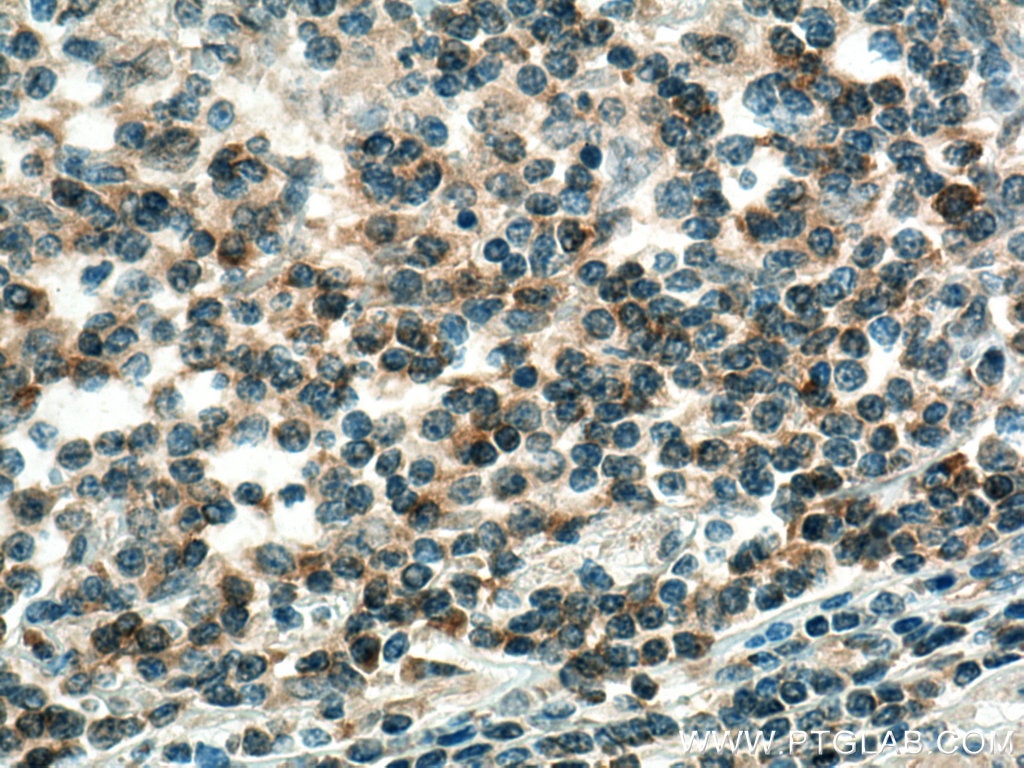

| Positive IHC detected in | human skin cancer tissue, human colon cancer tissue Note: suggested antigen retrieval with TE buffer pH 9.0; (*) Alternatively, antigen retrieval may be performed with citrate buffer pH 6.0 |

| Immunohistochemistry (IHC) | IHC : 1:200-1:800 |